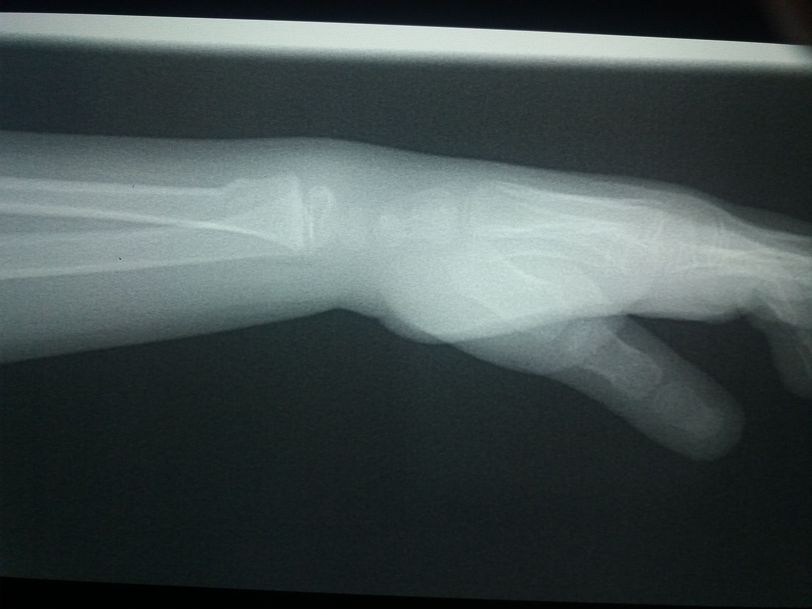

Fracture

Find the problem

It seems that carpal bones are detached from ulna and radius, maybe due to tear of triangular or collateral ligaments.

not detached its normal thing in children called grwoth plate

#distal part of radius